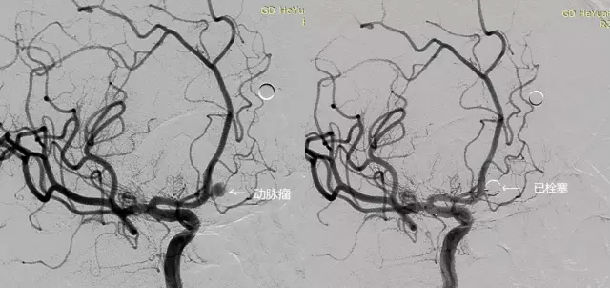

患者欧某,男,49岁,有洒精性肝硬化病史,因突发剧烈头痛伴呕吐4小时入住我院神经外科,术前诊断为前交通动脉瘤破裂并蛛网膜下腔出血。在我院神经外科急诊行颅内动脉瘤栓塞术,术程顺利,动脉瘤致密栓塞(图一),术后神经功能逐步康复。入院后12天突发呕血,量大,自述口渴,考虑肝硬化食管胃底静脉曲张、上消化道出血转入外五区,经积极止血,输血,护肝等积极支持治疗后,病情稍缓解,胃镜明确诊断,即安排送介入室,在局麻下行TIPS术,术后门静脉压力降低10cmH2o手术顺利,术后安返病房。

图1 前交通动脉瘤破裂栓塞术